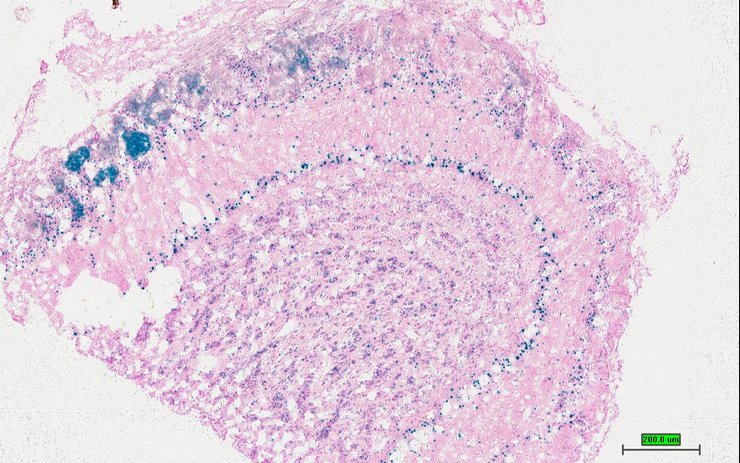

Specimen TCP_2460548: postnatal adult; Ptprstm1b(KOMP)Mbp/Ptprs+ (more )

Structure Level Pattern Image Note

TS28: skin Present TCP_2460548